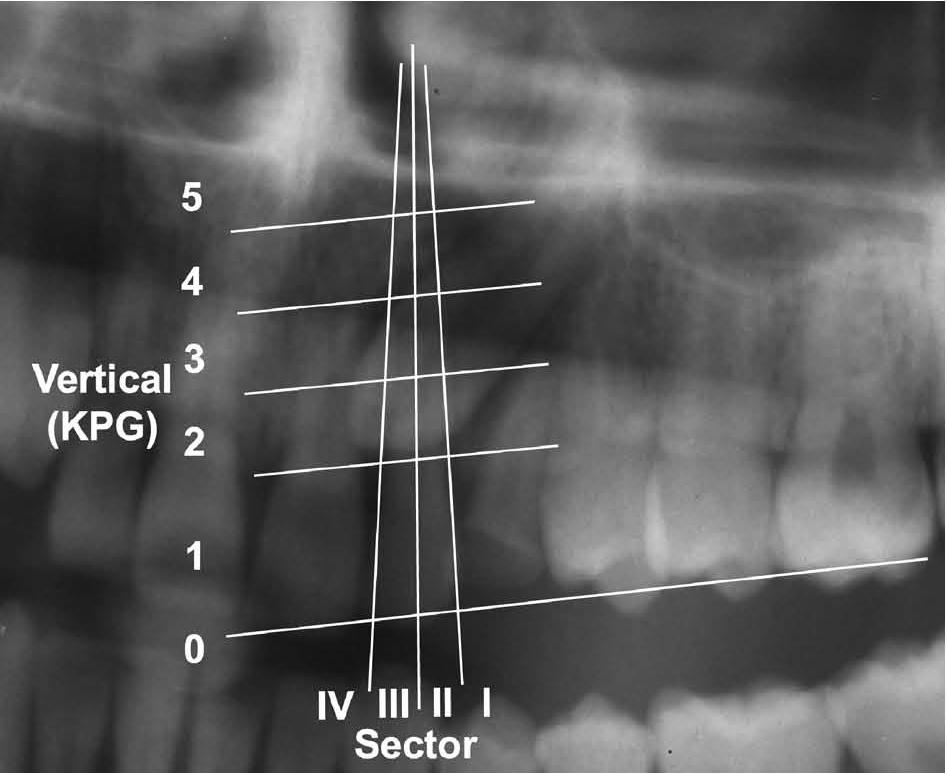

| Sector | ||

| I | 14 | 19 |

| II | 20 | 27 |

| III | 13 | 17 |

| IV | 26 | 35 |

| Vertical (KPG) | ||

| 1 | 9 | 12 |

| 2 | 46 | 63 |

| 3 | 14 | 19 |

| 4 | 4 | 5 |